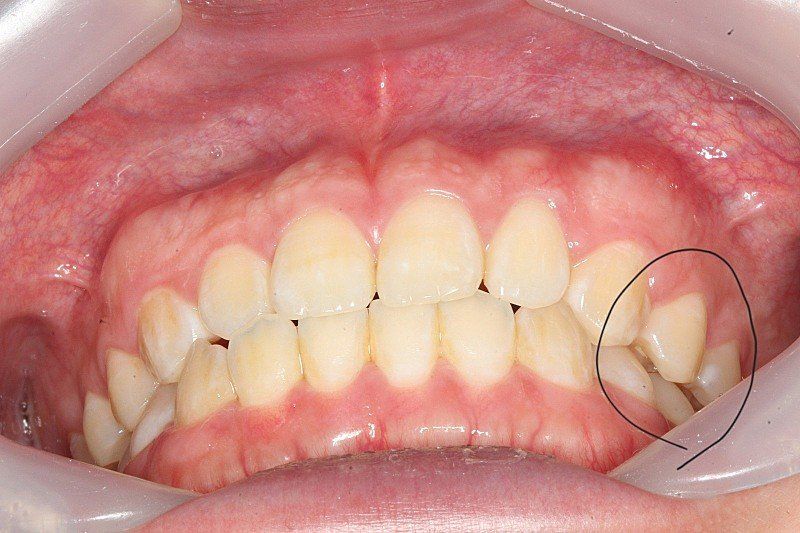

1.치아 교합이 어금니 소구치교합이 딱 안맞기도 하나요?

한쪽은 조금 떨어져있고 반대쪽은 딱 붙어있습니다

살짝 떨어져있는게 정상인지 딱 붙어있는게 정상교합인지 모르겠습니다

• 2번 째 사진

1. 치아와 치아가 서로 맞물릴 때 점과 점으로 만나 교합을 이룹니다. 따라서 사진에서 보는 바와 같이

약간의 공간이 생기는 것은 정상 범주에 속합니다.

치아의 교합은 균일하게 닿고 있는 것이 좋지만 교합이 약간 떠있어도 기능을 하는데 큰 문제가 없다면 정상적인 교합으로 간주되기도 합니다.